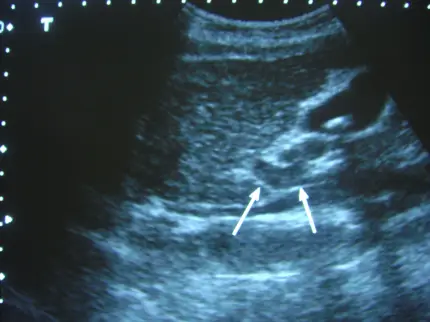

第二張圖(右上腹肝門區超音波)

- 影像右上方可見一串排列的高回聲小斑塊,伴隨後方聲影(acoustic shadowing),符合膽結石(gallstones)的典型特徵。

- 箭頭所指之圓形無回聲結構為直徑較大的門靜脈(portal vein),鄰近可見直徑較小的動脈管腔(hepatic artery),構成肝門三聯徵所謂的“Mickey Mouse sign”。